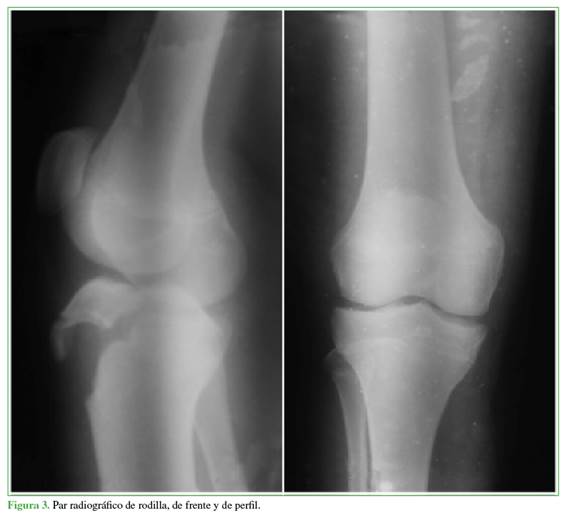

Varón de 13 años que refirió haber sufrido un traumatismo directo en la rodilla derecha durante la carrera en la práctica deportiva (fútbol), de un mes de evolución. En el examen físico, se observó una marcha antiálgica, asistida con muletas e inmovilizador de rodilla, edema en la región de la TAT, rótula alta y se detectó dolor tanto a la palpación como a la flexo-extensión. Un par radiográfico (Figura 3) y una comparativa contralateral constataron la avulsión de la TAT, tipo IIIA de la clasificación de Ogden. La tomografía computarizada mostró la avulsión de la TAT con un trazo que se extendía hasta la superficie articular de la tibia, con desplazamiento.